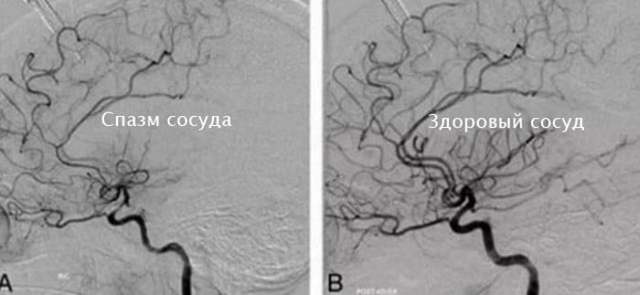

Спазм сосудов – внезапное сужение просвета кровянистых сосудов в мозгу. При его возникновении самочувствие больного редко ухудшается. Из-за кислородного голодания клеток мозга, развиваются различные нарушения работы центральной нервной системы. Спазмы сосудов в голове являются опасным состоянием, которое может вызвать развитие серьезных заболеваний.

Движение крови по сосудам происходит при сокращении и расслаблении их стенок. Спазм сосуда заключается в сокращении его стенок, после которого не следует расслабление. В результате чего затрудняется кровообращение, и также возникает характерный болевой синдром.

Расширение и сужение кровеносных сосудов – природный механизм перекачки крови. При спазме сосудов в мозге ухудшается кровообращение, а значит, что он испытывает недостаток кислорода. Данное состояние очень опасно. Ведь спазм сосудов не только является причиной боли и плохого самочувствия, но и может привести к инсульту.

Во время приступа артерии и более мелкие церебральные сосуды сокращаются, соответственно, кровоток замедляется, мозг испытывает кислородное голодание.